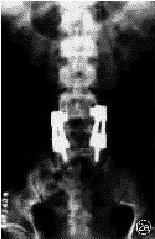

图2 术后6个月随访时,L4,5滑脱完全复位,骨痂生长良好,横突间植骨骨性融合 2a 术后X线正位片 2b 术后X线侧位片

本组21例,术后随访3~16个月,平均8.3个月。随访时症状完全消失者19例,临床满意率为90.5%(19/21),下腰痛症状完全改善率为84.6%(11/13),下肢疼痛改善率为100%(8/8),间歇性跛行改善率94.7%(18/19)。Ⅰ度滑脱完全复位率94.4%(17/18);Ⅱ度滑脱完全复位者2例,部分复位(70%)1例。本组21例滑脱完全复位率为90.5%(19/21)。2例部分复位者,1例术前因两个节段腰椎滑脱而行三个节段腰椎固定术,术后1年随访时,腰痛症状仅部分改善;另1例合并颈胸段椎管狭窄,其部分临床症状可能与此有关,术后6个月随访时,仍有部分跛行,为行颈胸椎MRI检查,取出SOCON内固定器,术中见固定节段融合良好,X线片显示无滑脱改变(图1,2)。本组无一例发生内固定失败。